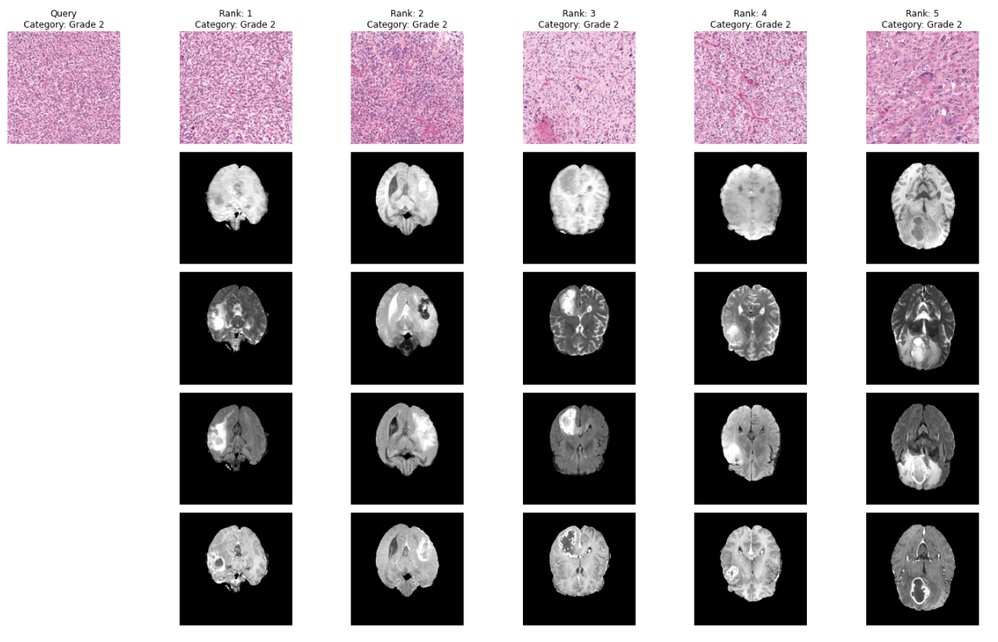

Once we can reliably generate embeddings, the rest of the search engine is straightforward: we compute embeddings for the pathology corpus, build a FAISS index (e.g., flat L2 for a baseline), and then run query → embedding → nearest neighbors to retrieve similar pathology cases. Example retrieval results across tumor grades (0–2) are shown in Figure 2. To make “similarity” more clinically meaningful, we optionally apply a lightweight adapter implemented as a small MLP, on top of the foundation embeddings. In the notebook, the adapter takes 1536-D GigaPath embeddings as input (in_channels=1536) and produces a compact 254-D representation (adapter_emb_size=254), trained with a simple 3-class objective (num_class=3, Grades 0/1/2). This is intentionally lightweight compared with retraining the foundation model: we only learn a small mapping from embeddings to a better-aligned space, then rebuild the FAISS index using the adapted vectors (gigapath_adapter_features) to improve retrieval relevance. The effect of this optimization is visualized in Figure 3, which contrasts the baseline embedding space with the adapter-optimized space.

Figure 2. Nearest-neighbor retrieval examples for Grade 0, Grade 1, and Grade 2 queries.